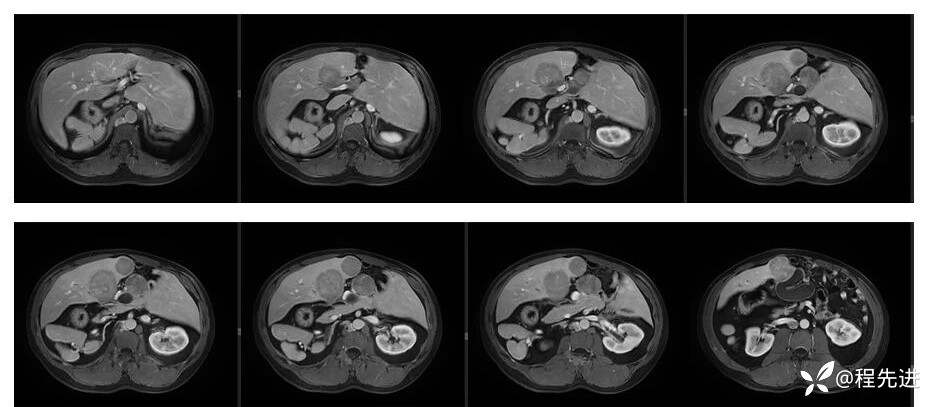

辅助检查:上腹部平扫+增强扫描提示:肝脏、脾脏、胰腺 、胃十二指肠左右倒置,脾脏形态失常,呈分叶团块状,考虑发育变异。肝左右交界区多发肿块,考虑:上皮样血管内皮瘤可能性大,或转移瘤?其它?请结合临床。脂肪肝。肝门胆管局限性扩张。胆囊折叠,壁稍增厚,慢性炎症?胰腺下方椭圆形结节,副脾?

影像检查